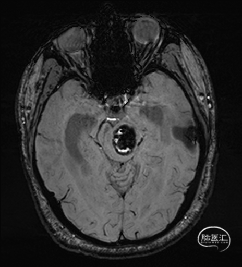

术前MRI检查

术前MRI检查提示左侧丘脑中脑海绵状血管瘤并卒中,梗阻性脑积水;

诊断:1.左侧丘脑中脑海绵状血管瘤并卒中,2.梗阻性脑积水;

年轻患者,较短时间内发生左侧丘脑二次出血,出现右侧面部及上肢麻木,复视,第二次出血后并发梗阻性脑积水,出现头痛。结合病史、神经系统体征、头颅CT及MRI检查,诊断左侧丘脑及中脑CM并卒中、脑积水明确,并导致了神经功能障碍,具备手术指征。

根据MRI及DTI显示,只有在丘脑与上丘之间的点(dot)进入病变才可能在切除病变时最大程度保护神经功能,由于上述原因,该“点”在术中显露极其困难,虽有导航指引,电生理监测的条件下,对术者的耐心、技术、经验及体能依然是极大的挑战;

本例患者磁共振检查清晰显示病变位于左侧丘脑中脑区域,且位于丘脑内下方向中脑顶盖延续,病变的上部、前部、外侧部都有重要的神经组织,因此,手术从上方、前方、外侧方向切除病变均难以实施;